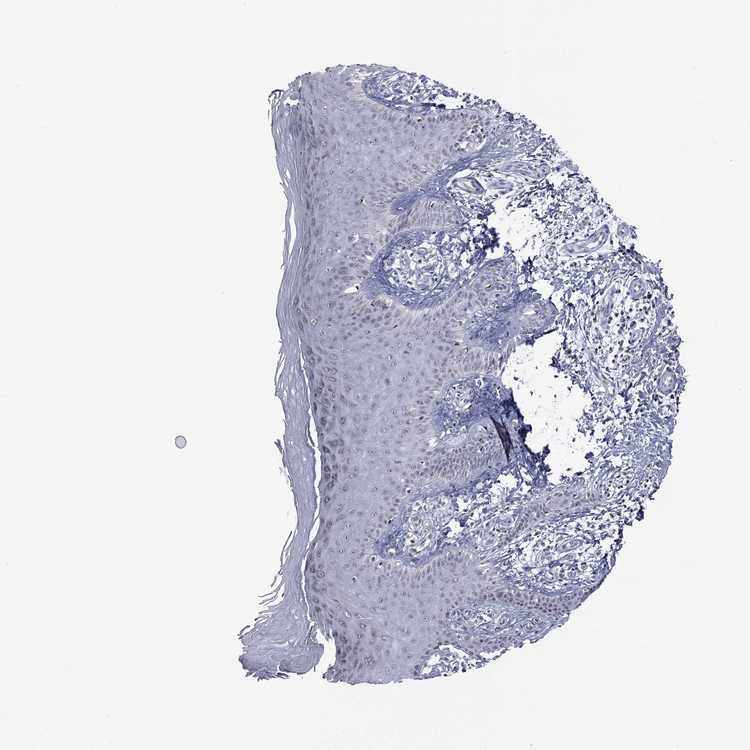

SKIN 1 - Antibody stainingi

Antibody staining in the annotated cell types in the current human tissue is reported as not detected, low, medium, or high, based on conventional immunohistochemistry profiling in selected tissues. This score is based on the combination of the staining intensity and fraction of stained cells.

Each image is clickable and will lead to virtual microscopy that enables deeper exploration of all samples and also displays staining intensity scores, fraction scores and subcellular localization as well as patient and tissue information for each sample.

Antibody HPA076284

Langerhans Medium

Fibroblasts Not detected

Keratinocytes Not detected

Melanocytes Not detected